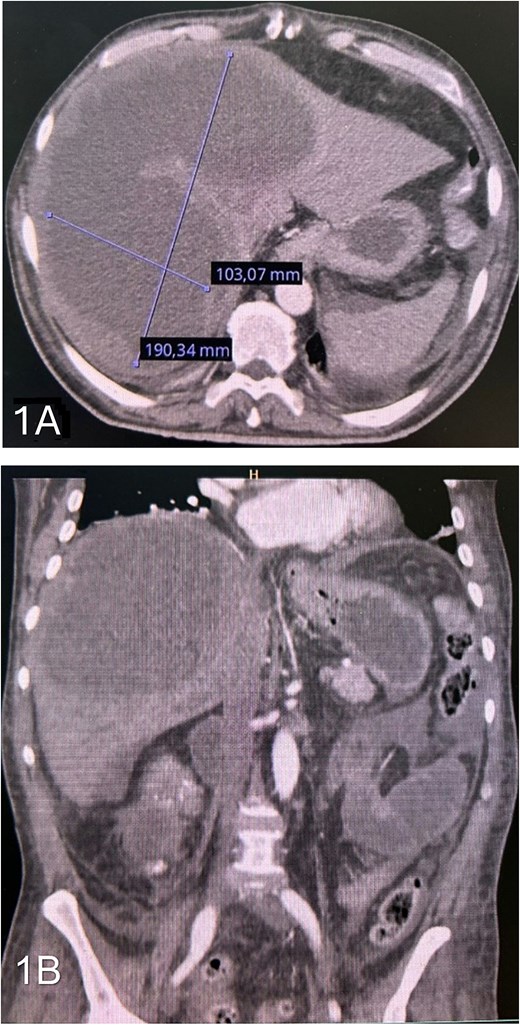

Contrast-enhanced computed tomography (CT) of the abdomen revealed a large hepatic abscess 190 × 103 mm, involving segments IVa, V, VII, and VIII, associated with dilated intestinal loops, and perihepatic fluid (Fig. 1).

(A) axial contrast-enhanced CT scan showing a large hepatic abscess involving segments IVa, V, VII, and VIII. (B) Coronal contrast-enhanced CT showing free fluid around the bowel and in the peritoneal cavity.